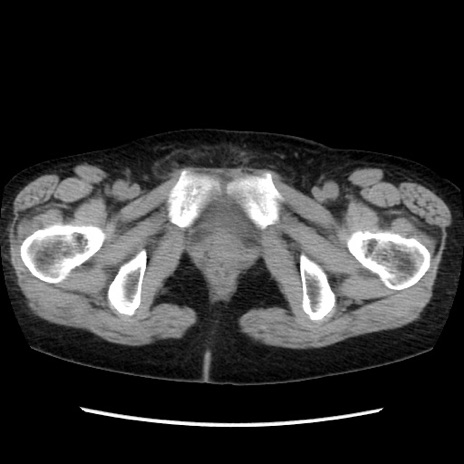

症例32(横断像)

【症例】40歳代 女性

【主訴】上腹部痛、嘔気・嘔吐

【現病歴】約9時間前頃から急に上腹部痛、嘔気、嘔吐が出現。改善しないため救急要請。

【既往歴】子宮頚癌(広汎子宮全摘術、放射線療法)、腸閉塞

【身体所見】腹部:平坦、軟、腸雑音亢進、上腹部を中心に腹部全体に圧痛あり。

【データ】WBC 8400、CRP 0.03